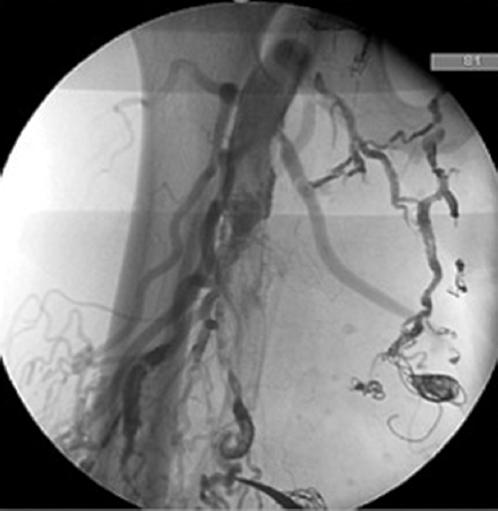

Open surgery was attempted for resection of accessible arteriovenous fistulae at the femoral bifurcation, fistulas between the femoral artery and vein were ligated and a selective arteriography was made clamping the superficial femoral and the profunda in different times, finding that all the remaining fistulous vessels were coming from the profunda femoris (Fig. 4). A final session was planned with selective catheter placement in the profunda femoris and embolization of feeding arteries with Onyx-34 and 2 coils, the last arteriography showed significant decrease in fistulous shunts (Fig. 3D). There were no complications documented in any of the sessions, and the patient was discharged in 24-48 h every time.

Figure 4 Fistulas between the femoral artery and vein were ligated and a selective arteriography was made clamping the superficial femoral and the profunda in different times, finding that all the remaining fistulous vessels were coming from the profunda femoris.